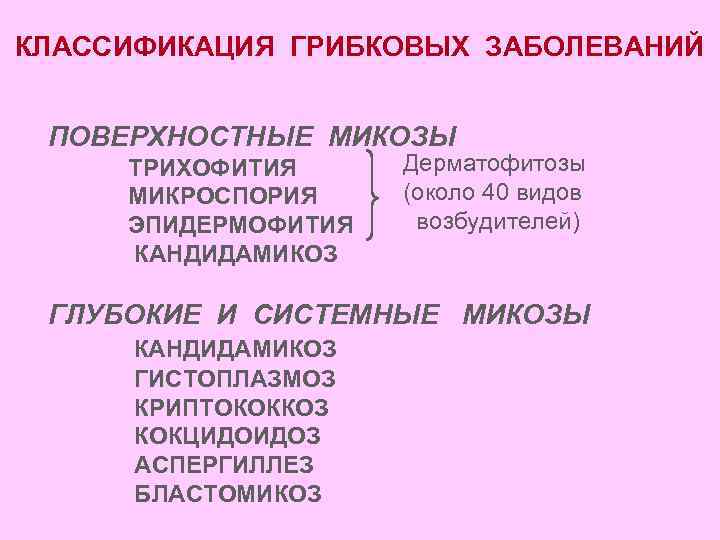

КЛАССИФИКАЦИЯ ГРИБКОВЫХ ЗАБОЛЕВАНИЙ ПОВЕРХНОСТНЫЕ МИКОЗЫ ТРИХОФИТИЯ МИКРОСПОРИЯ ЭПИДЕРМОФИТИЯ КАНДИДАМИКОЗ Дерматофитозы (около 40 видов возбудителей) ГЛУБОКИЕ И СИСТЕМНЫЕ МИКОЗЫ КАНДИДАМИКОЗ ГИСТОПЛАЗМОЗ КРИПТОКОККОЗ КОКЦИДОИДОЗ АСПЕРГИЛЛЕЗ БЛАСТОМИКОЗ